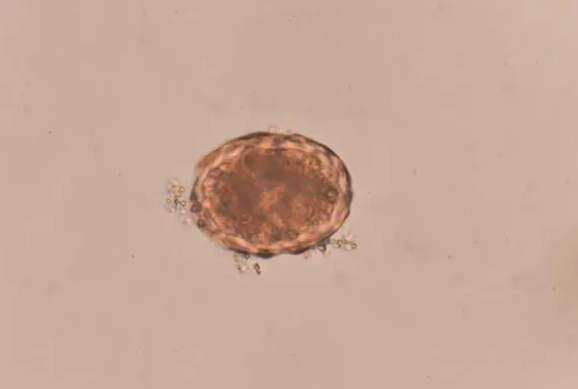

猫狗体内常见的6种寄生虫治疗方法和预防措施

很多宠物主人,看了很多科普文章后,也还是弄不懂寄生虫的种类、危害,以及如何治疗,因此本文主要以通俗易懂的方式给宠物主人,普及寄生虫的危害和如何预防治疗。